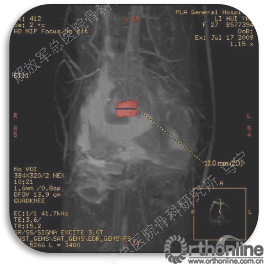

首先经过核磁的检查、评估,初步确定软骨损伤范围,利用T2maping检测序列对软骨的信号区分。图中我们可以看到软骨损伤的范围,并通过计算机计算出大概的面积。